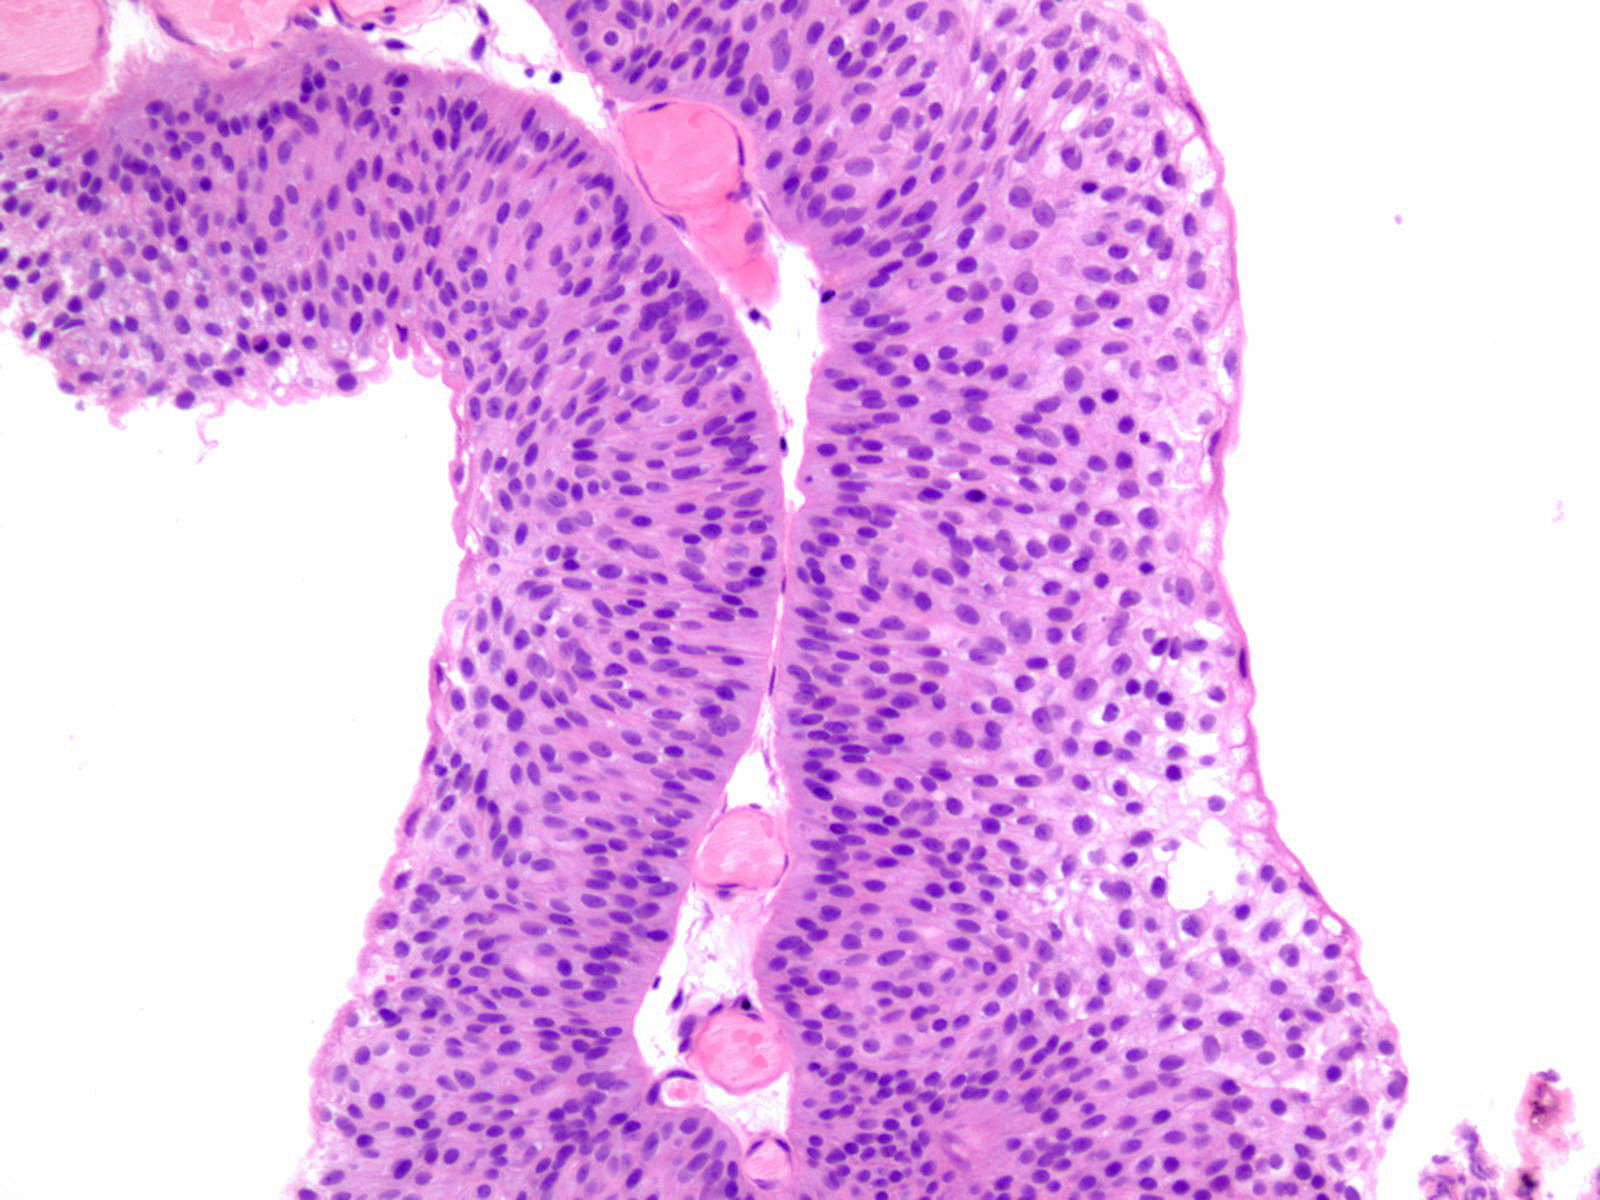

Bladder Papillary Lesions

Case ID: 121